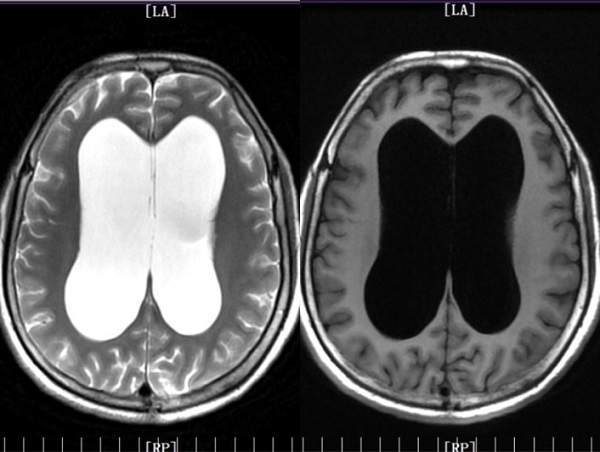

患者中年女性,以“间断头痛头晕5年余”入院,头颅MRI检查提示“幕上脑室系统扩大”。行磁共振3D FIESTA查可见“中脑导水管狭窄粘连,三脑室底受压下陷”。诊断为:梗阻性脑积水。